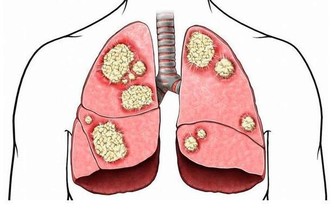

實行了LASIK後所產生的圓錐角膜目前在醫學上被認為是絕症,最後只能用角膜移植來解決問題!